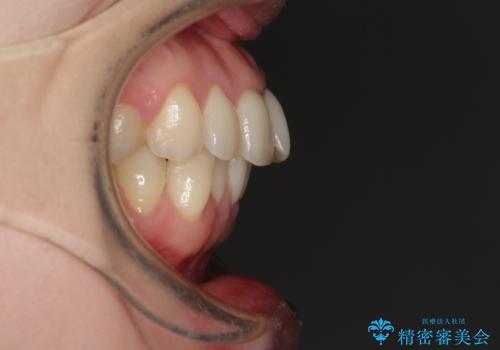

- 上下の前歯のデコボコを気にして来院された患者様です。

妊娠中であり、途中通院が難しくなる可能性があることから、インビザラインによる矯正治療を行うこととしました。

上下顎歯列全体の後方移動とIPR(歯と歯の間を削る)によってデコボコが解消するように設計しました。